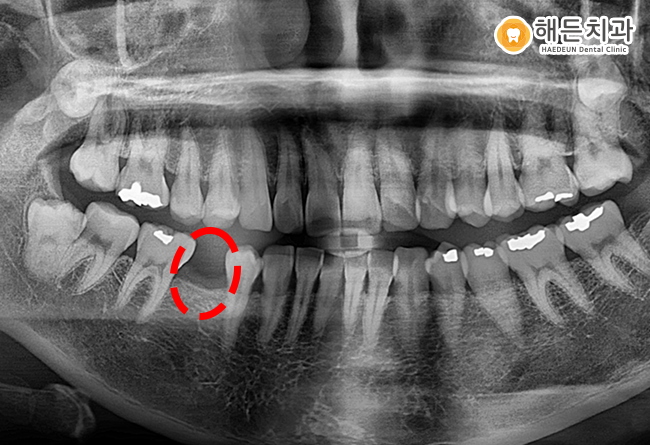

식립을 진행하기 전 검진해보니, 타치과에서 인레이 치료를 한 옆 대구치에 2차 우식이 진행 중이었습니다.

다행히 치수까지 충치가 진행되지 않아서 해당 치아는 레진 치료 등로 충치 치료를 계획하였습니다.

만약, 보철물 속에 2차 충치가 생기게 되면 눈으로 확인하기가 어려워 처음에 발견하기가 쉽지 않습니다.

파노라마 사진과 같이 식립 후 보철물 치료 전까지 치료를 한 상태입니다.

사진을 보시면 잇몸뼈와 임플란트가 잘 유착돼 있는 것을 확인할 수 있습니다.